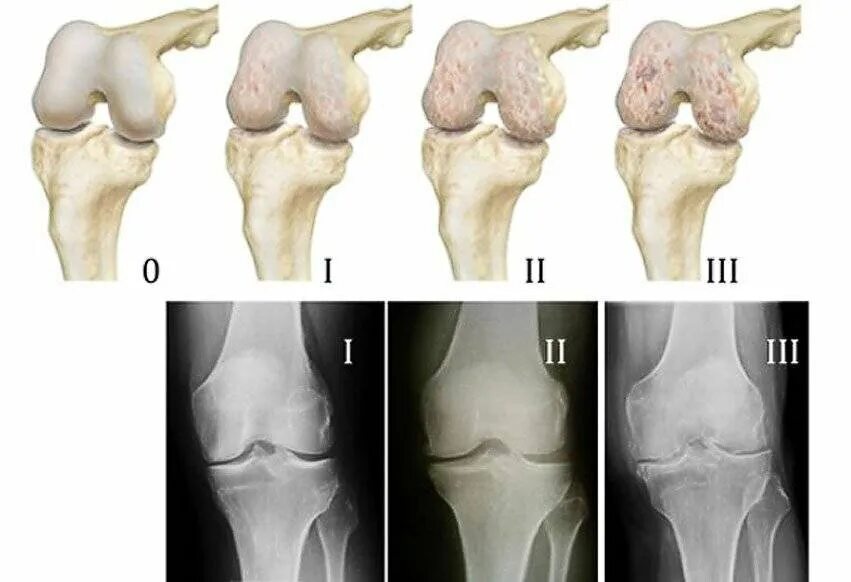

Деформирующий остеоартроз коленного сустава 1. деформирующий остеоартроз коленного сустава степени. деформирующий остеоартроз 1 стадия. стадии деформирующего остеоартроза коленных суставов.

Классификация остеоартроза коленного сустава. деформирующий остеоартроз механизм развития. артроз 1 степени коленного сустава классификация. деформирующий гонартроз 1 степени коленного сустава.

Деформирующий гонартроз коленного сустава. деформирующий артроз 2 степени. первичный гонартроз коленного сустава 1. гонартроз 1 степени по kellgren.

Келлгрен лоуренс. остеоартроз коленного сустава степени. артроз коленного сустава (гонартроз). классификация остеоартроза по kellgren-lawrence.